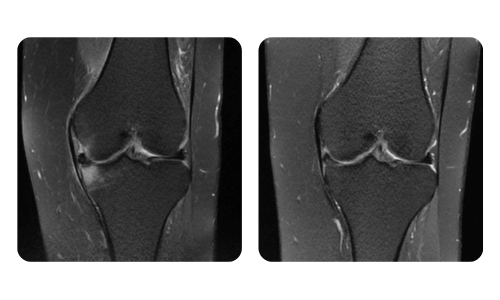

I progressi dei nostri pazienti, misurati prima e dopo la terapia iperbarica, riflettono l'efficacia e l'impatto positivo del trattamento. Scopri i risultati documentati della terapia iperbarica presso la clinica Hyperbarium Oradea, basati su valutazioni cliniche e dati oggettivi che evidenziano miglioramenti significativi in diverse condizioni.